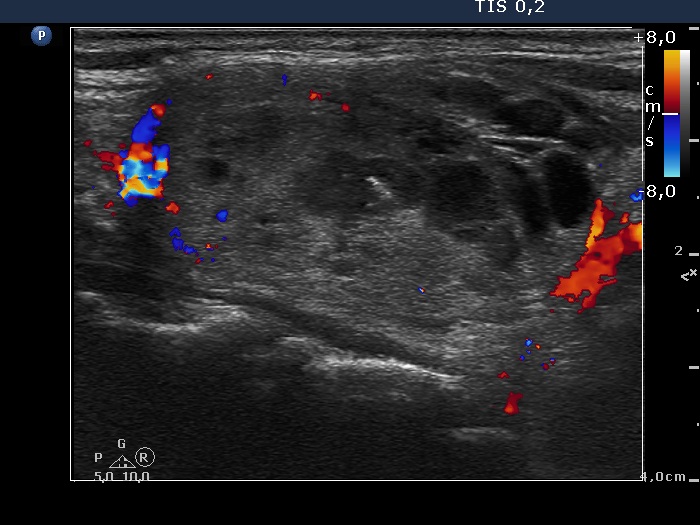

Study on 100 consecutive patients with thyroid nodule - case 006 (ultrasonographic picture 6)

Right lobe, longitudinal view, color Doppler mode.